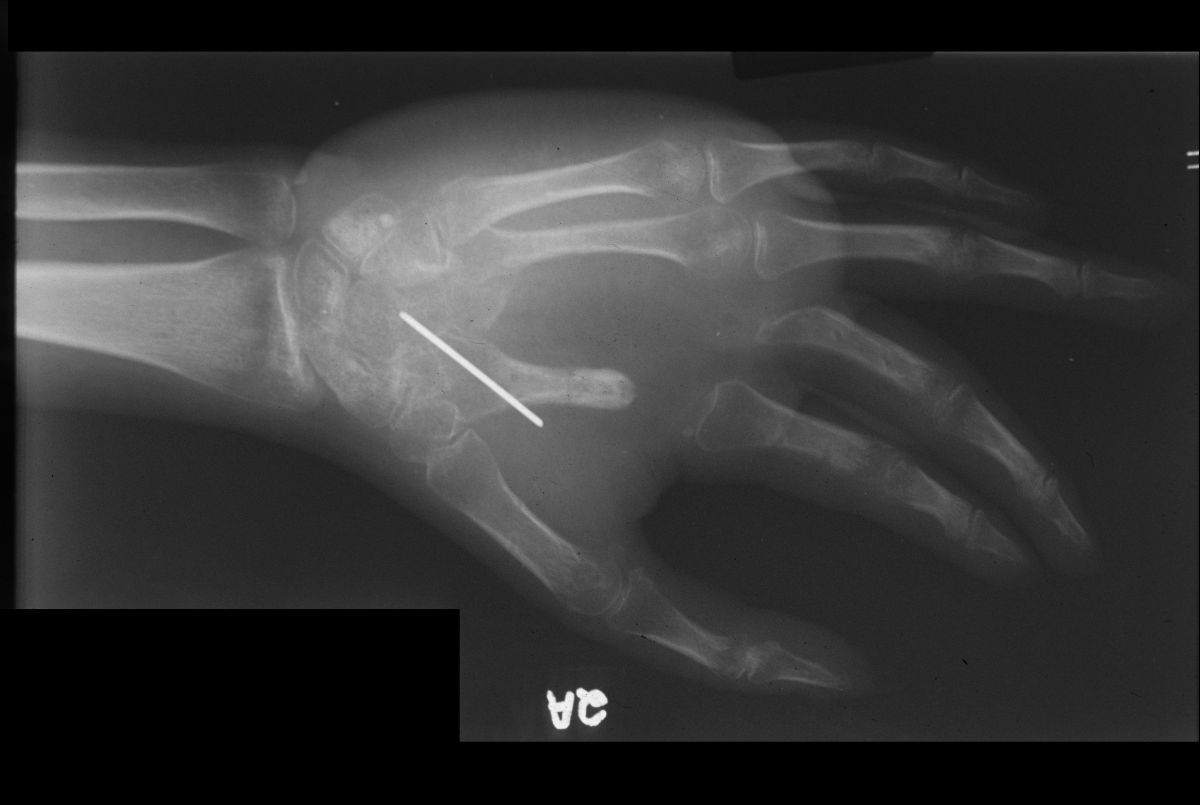

After debridement, the index and middle flexor tendons are visible in the base of the wound. The fingers were held out to length with an external fixator constructed from K-wires, suction tubing and methacrylate, and the soft tissue defect was closed with a latissimus dorsi myocutaneous free flap.

Progression of Xrays: injury; debridement; bone graft; after hardware removal: